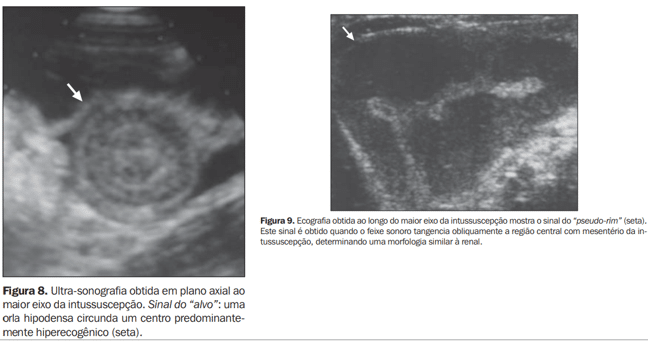

Entre os principais achados ultrassonográficos, destacam-se:

- Sinal do alvo (target sign): visualizado em cortes transversais, caracteriza-se por múltiplos anéis concêntricos com hiperecogenicidade periférica e centro hipoecogênico.

- Sinal do pseudorrim: observado em cortes longitudinais, lembra um rim, com camadas intestinais invaginadas simulando o parênquima e a pelve renal.